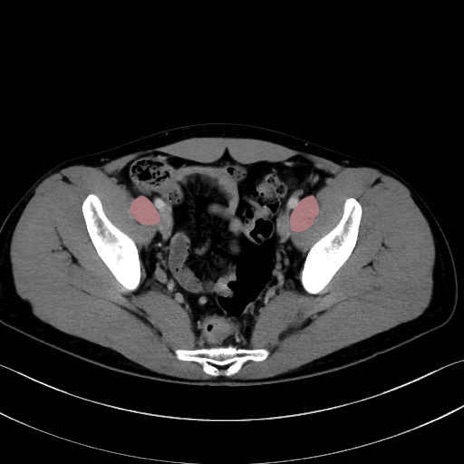

2. 腸腰筋群と骨盤底筋

大腰筋 (Psoas major)

腸骨筋 (Iliacus)

肛門挙筋 (Levator ani)